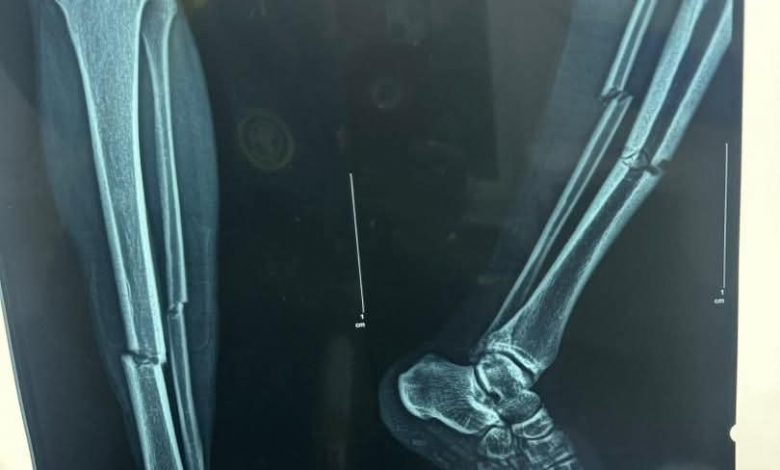

في تفاصيل التقرير الطبي للاعب سانت لوبوبو الكنغولي تؤكد تعرض اللاعب لكسر مركب حيث أوصى الفريق الطبي الذي عاين الحالة بضرورة أن يخضع اللاعب لعملية جراحية عاجلة.